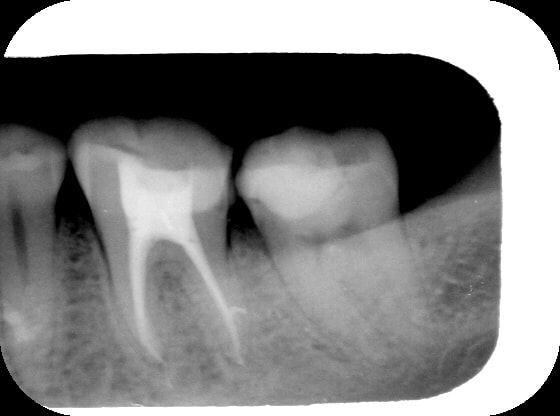

dedicace pour damdam ;)

mon endo du jour...

tech: reconstruction de la dent avant endo au fuji IX, pose de la digue, hypo camérale, laser Dmed caméral, lime 8, 10, 15, 20, 25 manuelles puis protaper jusqu'à F2, le tout sous loc d' apex et glyde, puis hypo-laser fibre 200m C+ en remontant, pointe de papier sterile 6%, laser pour secher, pate endo lentulo, laser en remontant, re-lentulo, maitre cone F2, laser grosse fibre G- sur les cones de gutta pour les rechauffer, fouloir pour condensation à chaud.... voilou, ma tech n a plus de secret pour vous.